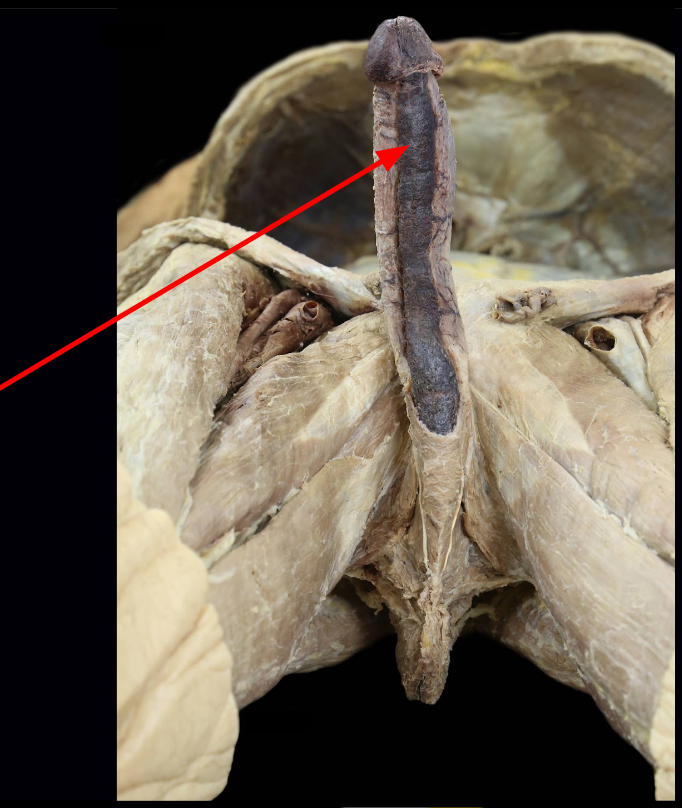

Bulb of Penis

Corpus Cavernosum

Corpus spongiosum